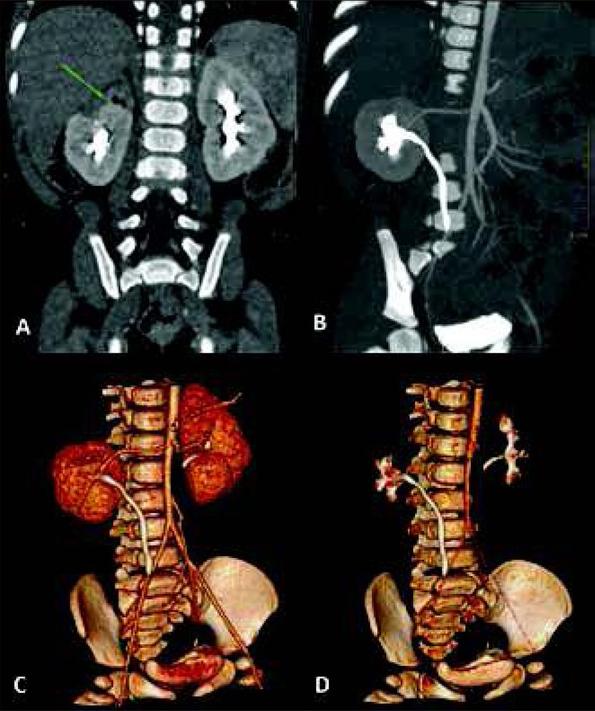

Combination of vascular and excretory phases (Protocol 3) provides the most complex visualization of the urinary system. It allows to asses abnormalities of the collecting system, with additional information about renal vascularity and general renal anatomy. It appears very useful especially before planned surgical intervention, e.g. heminephrectomy in duplicated collecting systems, where renal vessels and borders between both parts of the kidney should be evaluated (fig. 2). Vascular phase in this technique is not a “pure” CT-angiography, and it allows to assess renal parenchyma as well - higher heart rates in children will early enhance renal parenchyma in cortico-medullary phase [13]. Also, this protocol allows to detect crossing vessels as the cause of hydronephrosis [14, 15]. In comparison to other protocols, Protocol 3 will directly visualize the additional renal artery crossing and compressing the proximal ureter (fig. 3).

One-phase split-bolus CTU performed before planned surgical intervention in an 8-month-old girl with dys-plastic upper pole of duplicated right kidney. Coronal and volume reconstructions (A-D) show renal anatomy with dysplastic parenchyma (green arrow) and anatomy of vessels and lower collecting system.

Ryc. 2. Jednofazowa Uro-TK z podzielonym bolusem środka kontrastowego wykonana u 8-miesięcznej dziewczynki przed planowaną operacją heminefrektomii z powodu dysplazji górnego układu zdwojonej nerki prawej. Rekonstrukcje czołowe i objętościowe (A-D) przedstawiają anatomię nerki z dysplastycznym miąższem (zielona strzałka) oraz anatomię naczyń i dolnego układu zbiorczego nerki.